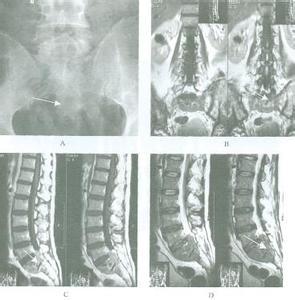

1.X线检查

原发性淋巴的X线表现多为溶性,“虫噬样”改变,在正常组织和病变组织之间有明显的分界限,部分病人有皮质的破坏和缺损,但较少有膜反应,还有部分病人表现为分离,即组织的正常部分与病变部分分离,亦可表现为病理骨折

3.MRI

骼系统的病变为破性,溶性,部分溶和部分硬化性及皮质的改变等多种表现,MRI对于原发性淋巴的诊断敏感性较高,能发现其他检查阴性的原发性淋巴,同时,它能发现周围结缔组织的病变。

本病的临床表现为非特异性,对于局部骨痛周围组织肿胀,或局部触及肿块,易发生病理骨折的患者,可怀疑本病。骼扫描阳性MRI显示占位性病变,在进骼活检前应考虑原发性淋巴的可能性以便采取足够的材料进病理检查确诊需要病理活检。但是手术活检会增大病理骨折的可能性。大部分原发性淋巴表现为IE期(60%)Ⅳ期(40%)。